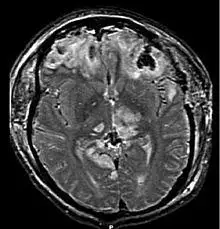

MRI scan showing damage due to brain herniation after TBI[2]

A large percentage of the people killed by brain trauma do not die right away but rather days to weeks after the event;[70] rather than improving after being hospitalized, some 40% of TBI patients deteriorate.[71] Primary brain injury (the damage that occurs at the moment of trauma when tissues and blood vessels are stretched, compressed, and torn) is not adequate to explain this deterioration; rather, it is caused by secondary injury, a complex set of cellular processes and biochemical cascades that occur in the minutes to days following the trauma.[72] These secondary processes can dramatically worsen the damage caused by primary injury[62] and account for the greatest number of TBI deaths occurring in hospitals.[39]